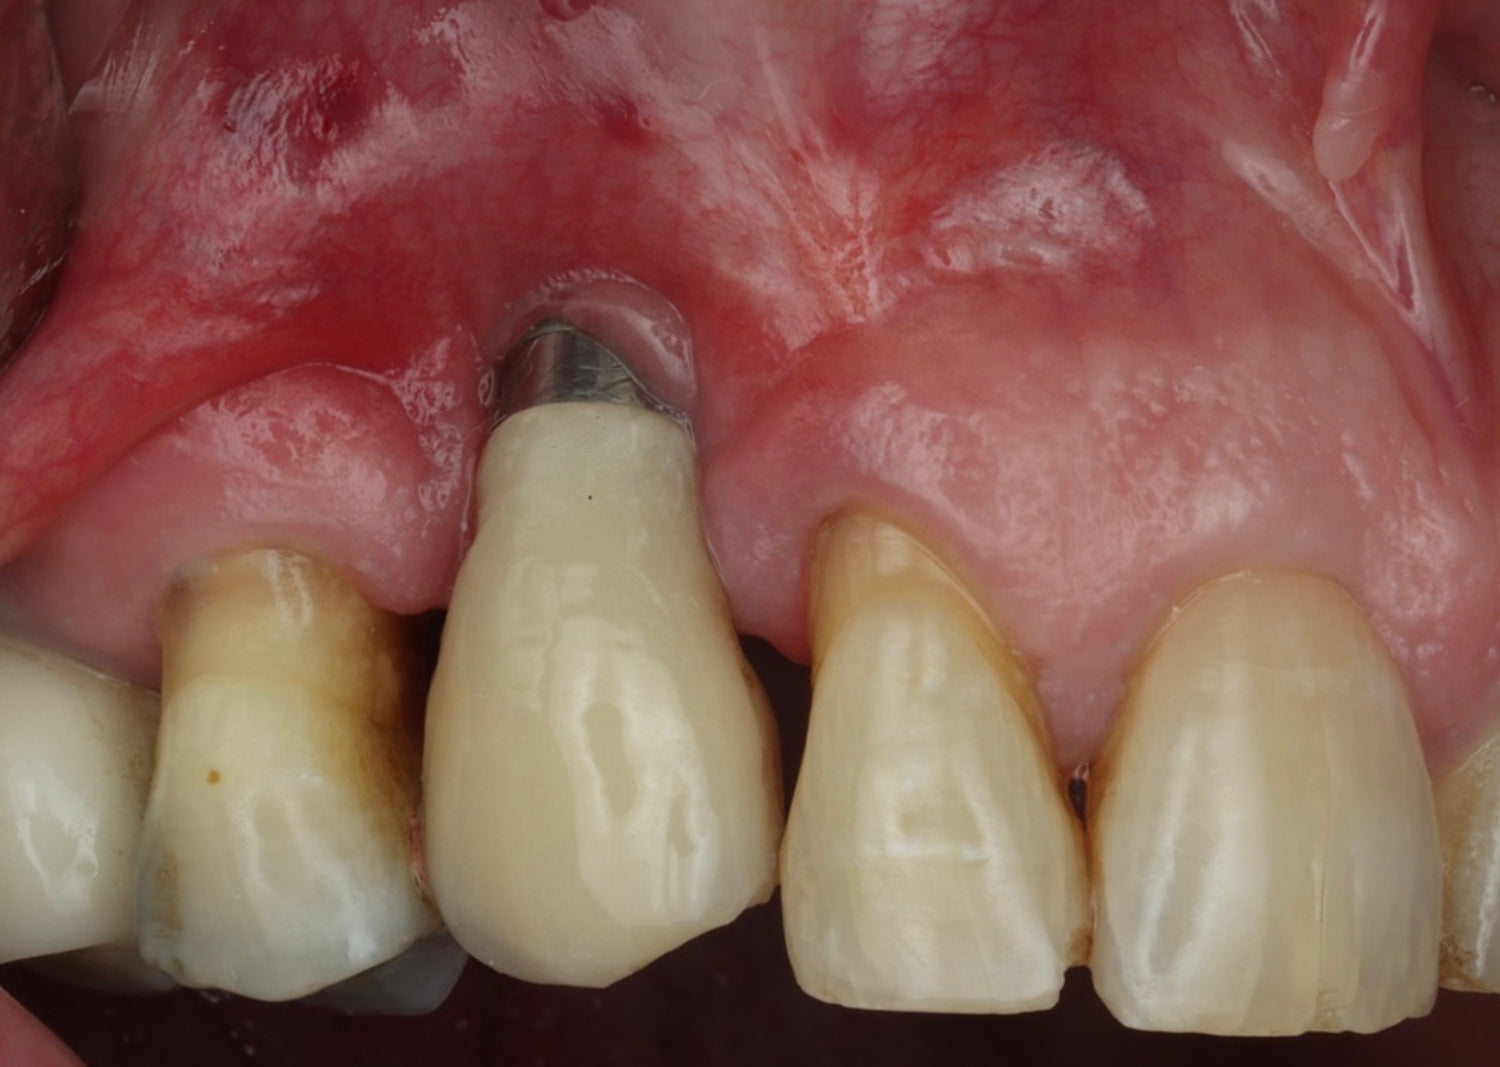

- Develop a thorough understanding of the critical soft tissue parameters that determine implant success

- Gain practical experience in soft tissue management and augmentation techniques for optimal peri-implant outcomes

- Explore the science behind Partial Extraction Therapy and understand its emergence as the gold standard in modern implantology

- Master Partial Extraction Therapy through systematic, step-by-step instruction and hands-on practice